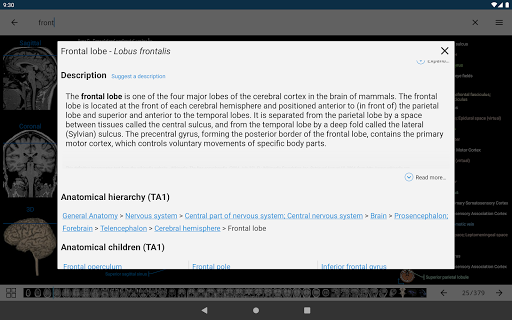

*Improved visibility of anatomical parts definitions

*Browse between anatomical parts using description links

-In the details view of an anatomical structure related terms are now displayed

- You can now hide structures one by one (new button inside the description popup) and display them again in the right menu